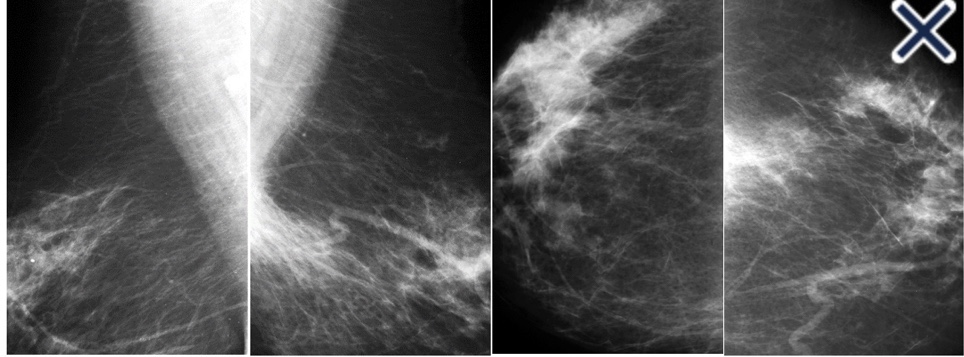

Bilateral diagnostic mammogram images

• Lacking calcifications and a central tumor mass:

• These cancers are notoriously difficult to perceive on mammogram:

• Even when they are large and palpable or when they occur in fatty involuted breasts: